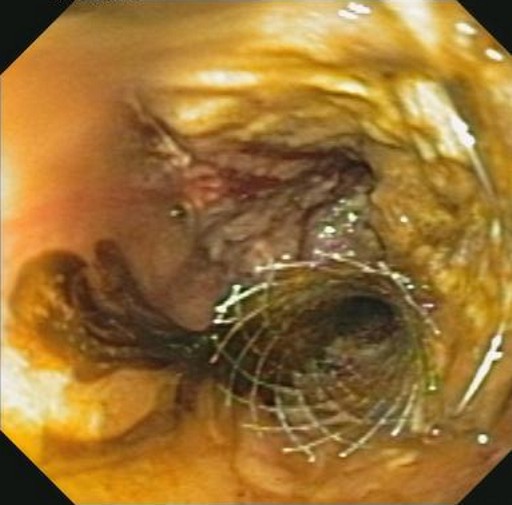

Thus, EUS-guided transduodenal biliary drainage (EUSBD) was performed. A linear array echoendoscope (GF-UCT140, Olympus America, Center Valley, PA, USA) was placed in the duodenal bulb allowing visualization of a dilated common bile duct (Figure 1). A 19-gauge FNA needle (Wilson-Cook Endoscopy, Winston-Salem, NC, USA) was used to perform a transduodenal puncture of the common bile duct through the proximal end of the duodenal stent. Bile was aspirated and a cholangiogram demonstrated good filling of the right and left duct systems with no evidence of a stricture proximal to the puncture site (Figure 2). Under fluoroscopy, a 0.035-inch straight guidewire (Jagwire, Boston Scientific Corporation, Natick, MA, USA) was passed into the biliary tree and directed toward the hilum. The FNA needle was exchanged for a biliary dilating balloon (Hurricane RX, Boston Scientific Corporation, Natick, MA, USA). The choledochoduodenostomy tract was dilated to 6 mm. A 10x60 mm fully covered self-expanding metal biliary stent (Wallfex®, Boston Scientific Corporation, Natick, MA, USA) was placed over the guidewire and deployed under fluoroscopy. One cm of the stent was left protruding into the duodenal bulb through the mesh at the proximal end of the duodenal stent (Figure 3). Good bile and contrast efflux was seen. The final fluoroscopic image did not demonstrate a bile leak (Figure 4). Post-procedure CT imaging demonstrated good positioning of the biliary stent and no evidence of a bile leak (Figure 5).

Figure 3. Deployed metal biliary stent protruding through mesh of duodenal wall stent. |